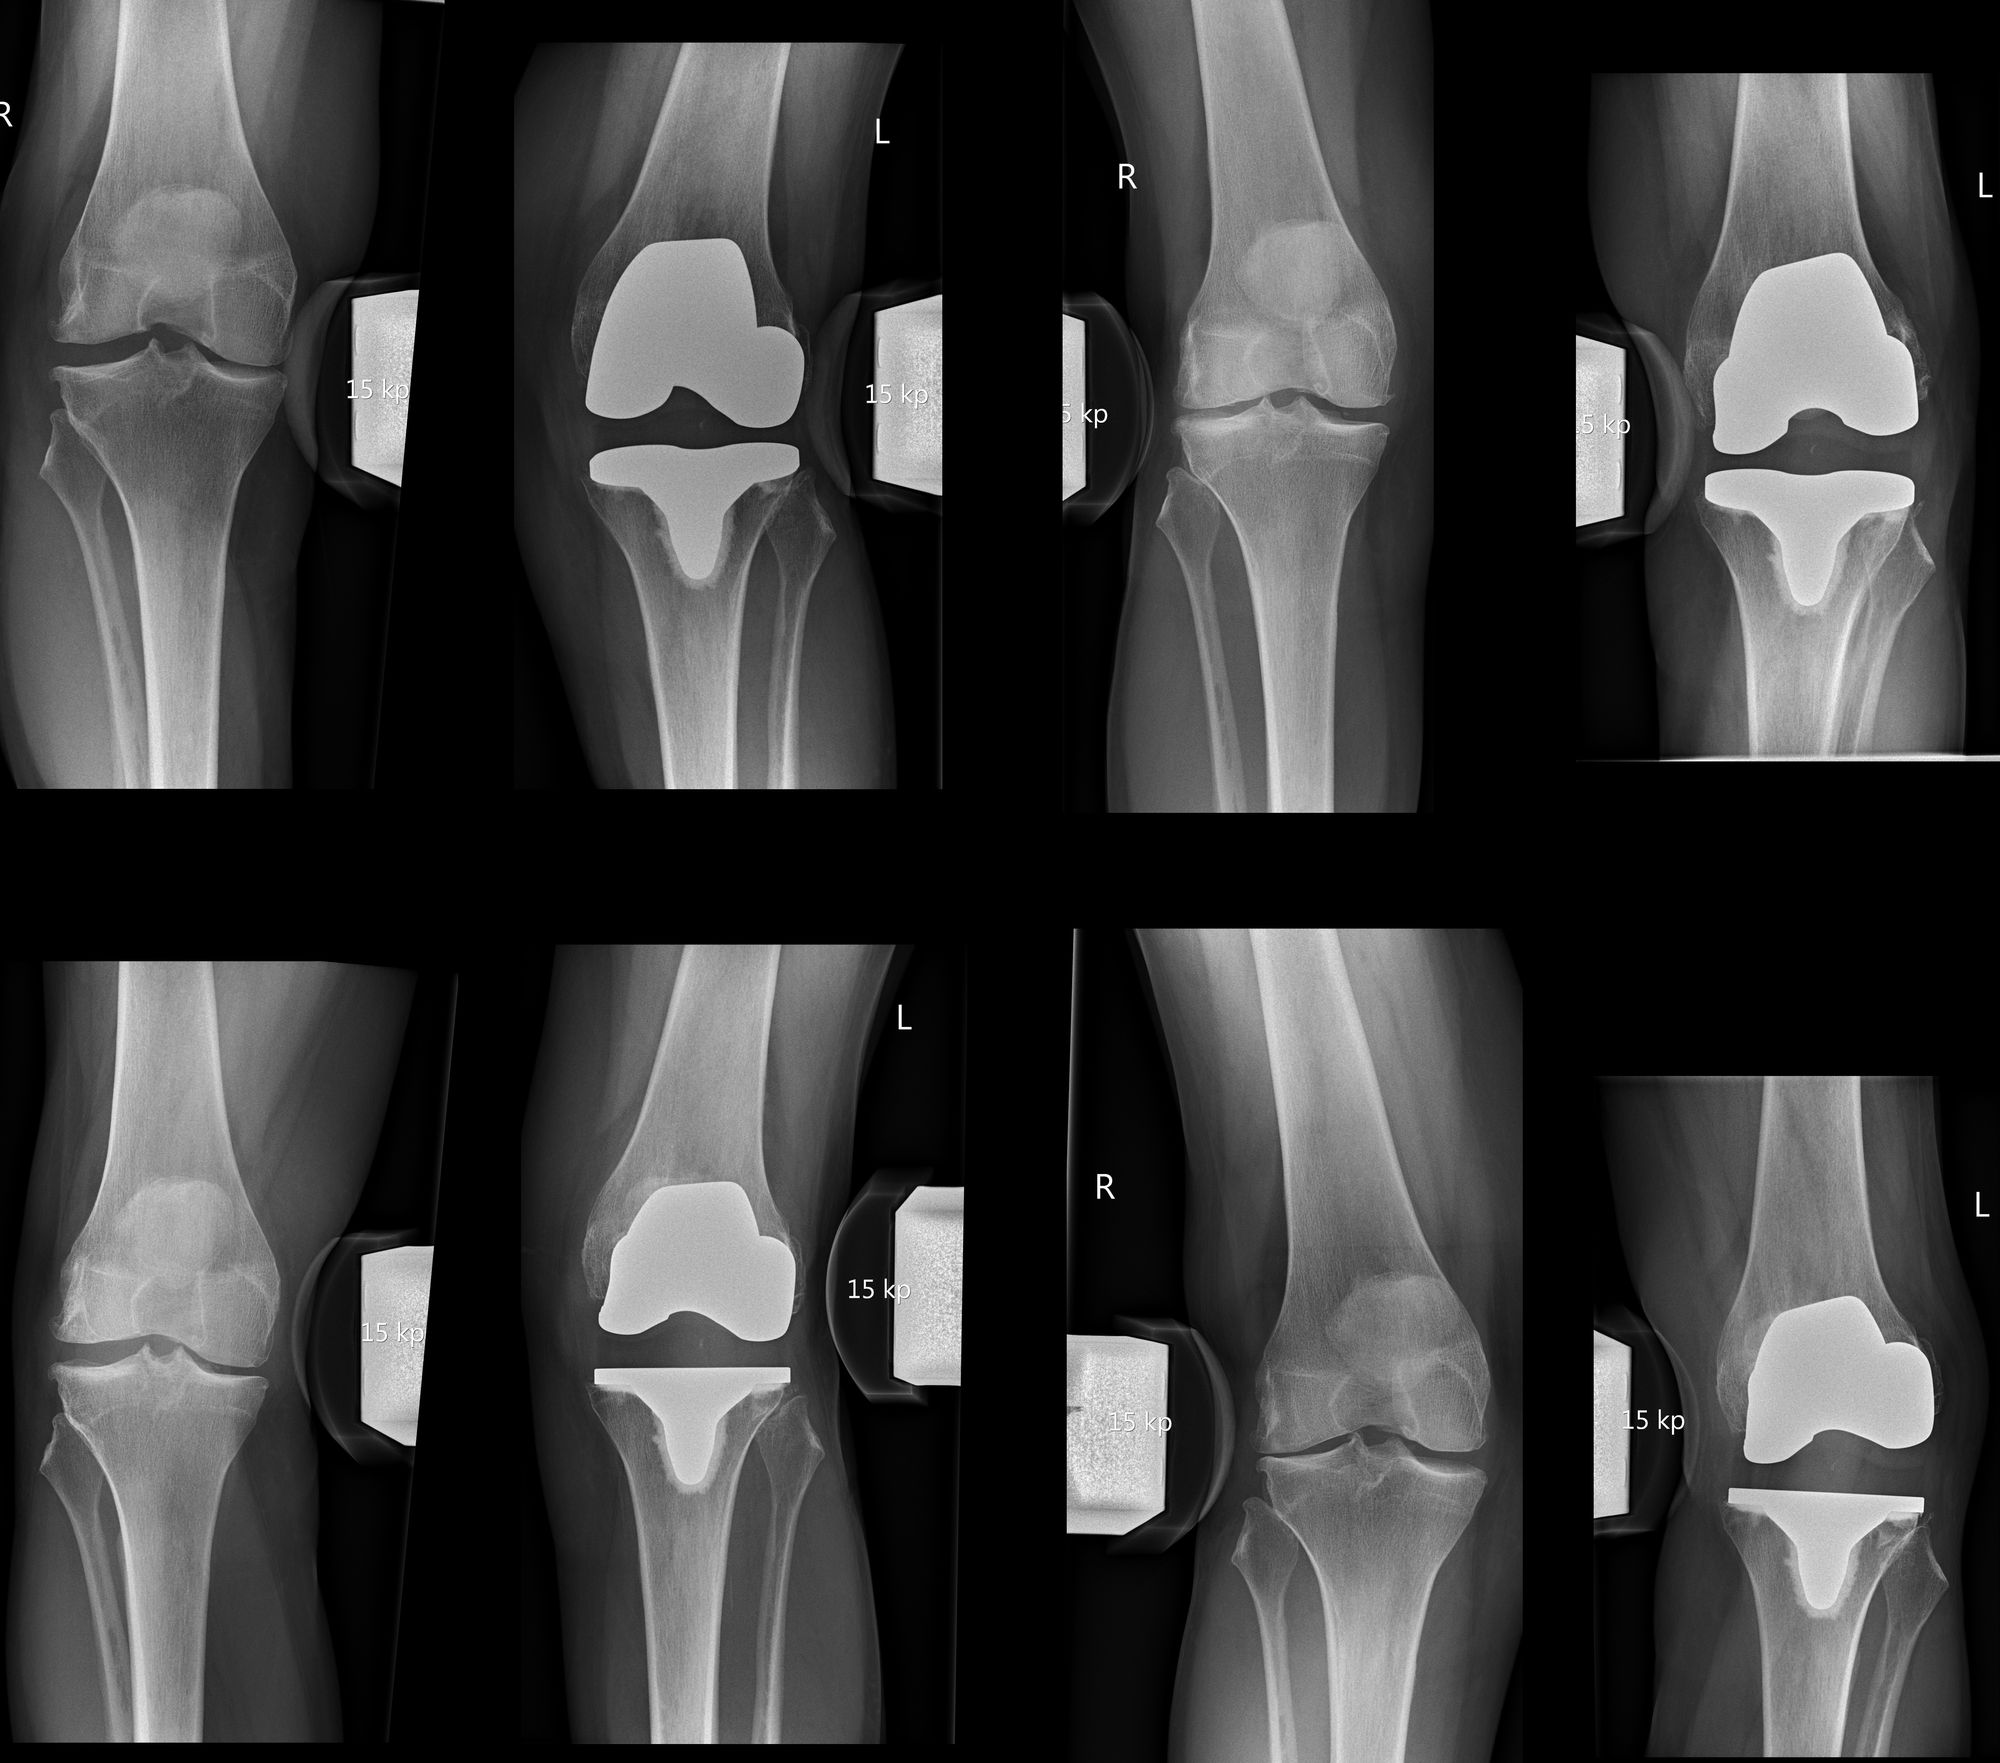

Assessment of preoperative radiographs is important as the degree of preoperative osteoarthritis is known to be an important predictor of outcome after TKA and these give insight into the change of alignment (4,5). If a knee problem is suspected standard radiographs (anterior-posterior and lateral weight bearing, patellar skyline view) should be performed. A frank component malposition, polyethylene wear, component over- or undersizing, component overhang, notching, periprosthetic fractures, overstuffing or extensive loosening can be detected. Whole leg radiographs are necessary for the assessment of the mechanical and anatomical knee axes. A patella baja or alta can be evaluated on lateral radiographs with the knee in 30° flexion. Stress radiographs in comparison to the contralateral side or fluoroscopy are performed in suspicion of instability or impingement (Fig 2) (6).

Stress radiographs should be performed in full extension and 15-20° flexion for varus-valgus stress and in 30° and 90° flexion for anterior-posterior stress (6). A Kanekasu view x-ray is helpful to detect asymmetric medial or lateral flexion instabilities. In all cases preoperative radiographs should be assessed for the degree of OA. It is also increasingly important to analyse the preoperative individual knee phenotype as we have understood that postoperative alignment and laxity can only be interpreted when you know the preoperative situation (4,7).